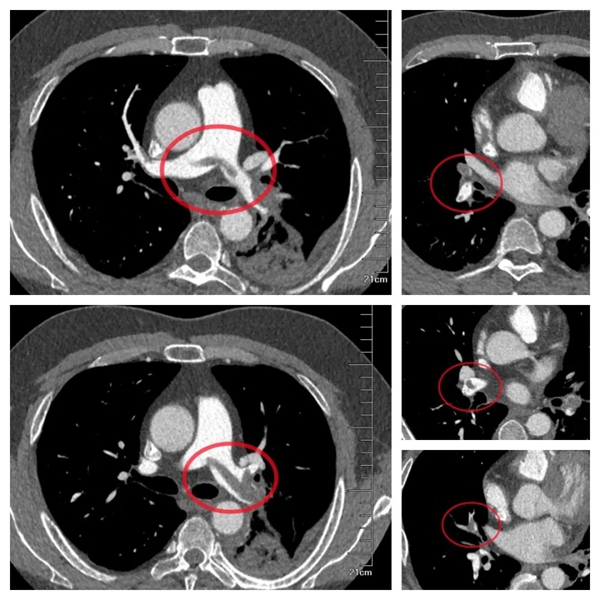

為明確診斷,醫(yī)生迅速為小李安排下肢血管彩超檢查,結(jié)果證實了擔(dān)憂:右側(cè)小腿肌肉內(nèi)靜脈附壁血栓,右下肢深靜脈血栓形成,且血栓頭端部分游離,隨時可能脫落引發(fā)致命性肺栓塞。進(jìn)一步的血?dú)夥治鲲@示,小李存在嚴(yán)重低氧血癥,強(qiáng)化肺動脈 CTA 更提示雙肺已出現(xiàn)大量血栓,救治刻不容緩!

△強(qiáng)化肺動脈 CTA 提示雙肺已出現(xiàn)大量血栓